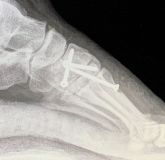

5. Fracture of the left tarsometatarsal joint in a 33-year-old male.

Treatment: Open reduction internal fixation

I. Before surgery, 3D reconstruction of CT scan indicates the Lisfranc injury II. Post-surgery, anteroposterior view of foot with the metal work III. Post-surgery, lateral view of foot with the metal work